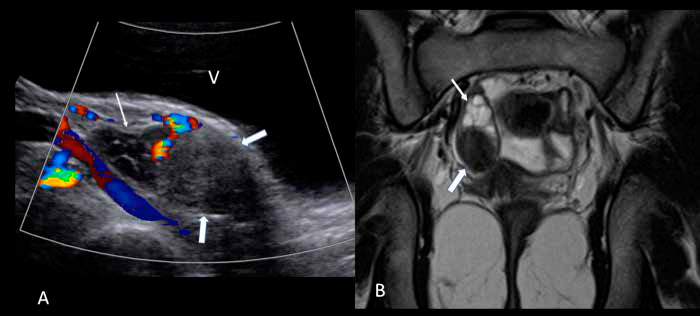

Se realiza RM de abdomen y pelvis que muestra las glándulas suprarrenales normales y una imagen nodular sólida de 2.1x1.6 cm en el ovario derecho (Figura 1), demostrada posteriormente con ecografía pelviana (Figura 1).

Figura 1. (A) Ultrasonografía pelviana muestra el ovario derecho aumentado de volumen, con una lesión sólida, heterogénea y sin flujo vascular en el polo inferior

(flechas gruesas) y folículos de aspecto normal en el polo superior (flechas delgadas). (B) RM de pelvis en corte coronal y en secuencia ponderada en T2, muestra

lesión hipointensa del ovario derecho (flechas gruesas) y los folículos en el polo superior (flechas delgadas).Discusión